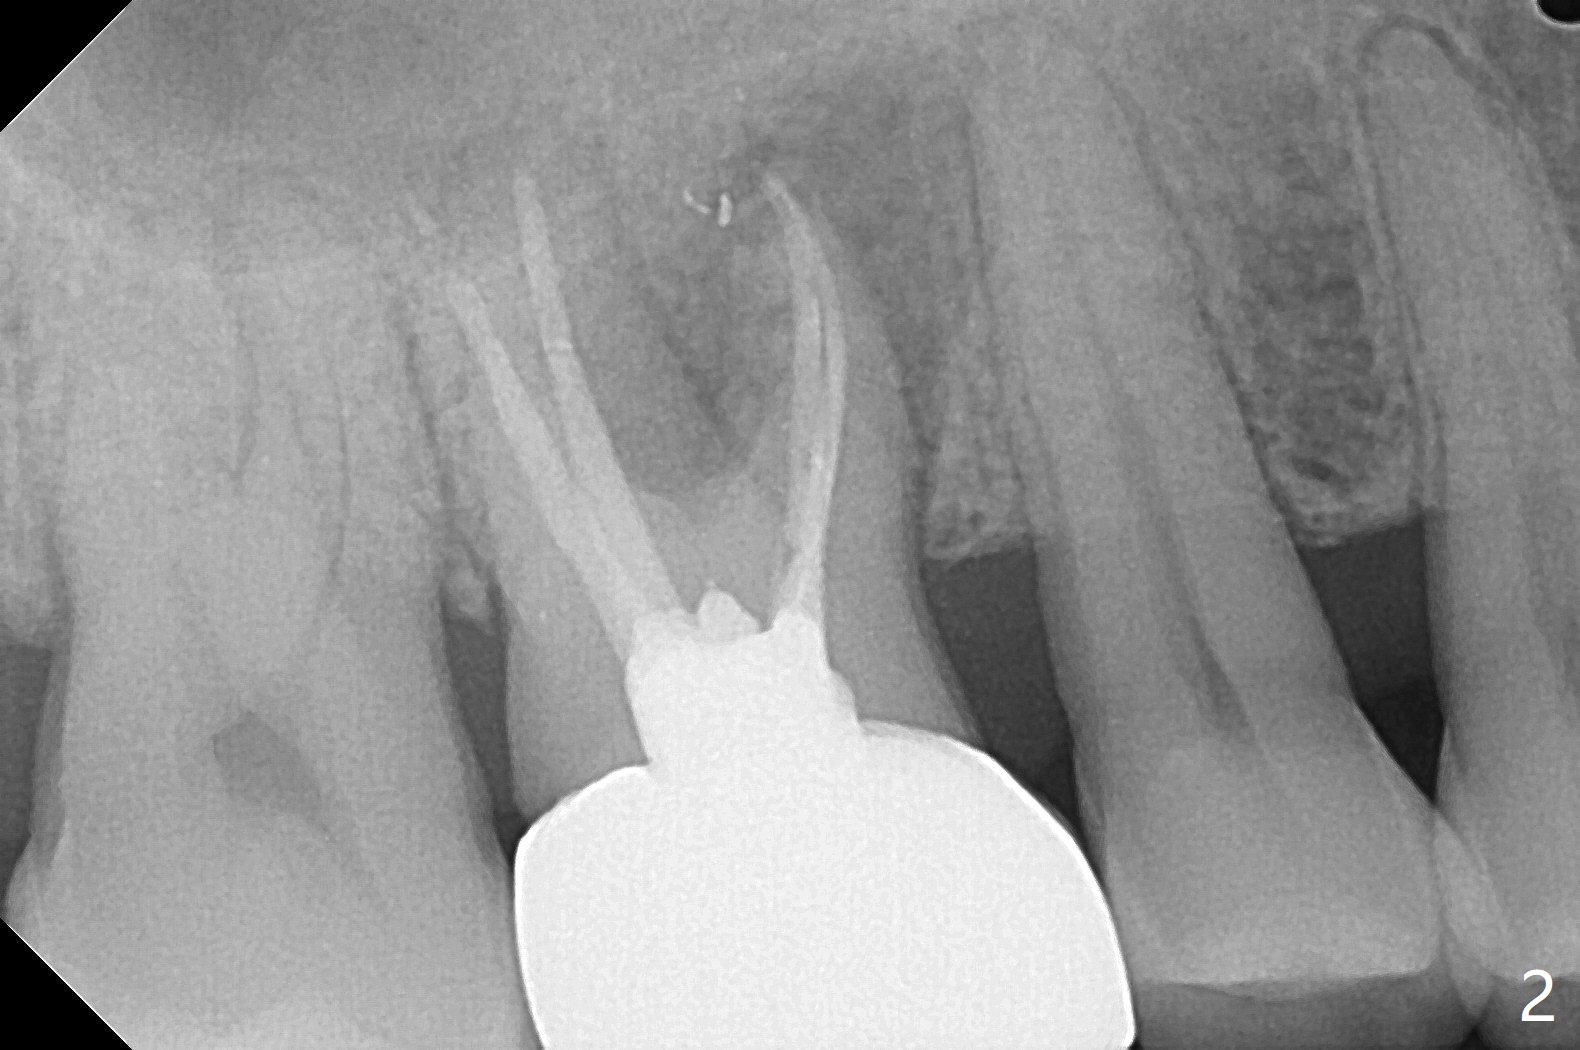

60岁男右上6出现脓包(图一),颊侧牙周袋深9毫米,指向近中颊侧根尖,根尖片(图二)和CT(图三(去除牙冠后))显示巨大近中颊侧根周骨质吸收,但是松动度低,一度想做根切。最佳植牙位点偏远中腭侧(图四),植体偏小,稳定性差,使用临时基台制作牙合面低的临时牙冠,目的包括固定粘性骨粉和防止邻牙移位。半张PRF膜用于上颌窦提升,另外半张用于覆盖牙槽窝开口的骨粉。局部使用抗菌素(Arestin),十九天后瘘道消失,根切,植骨可能成功。